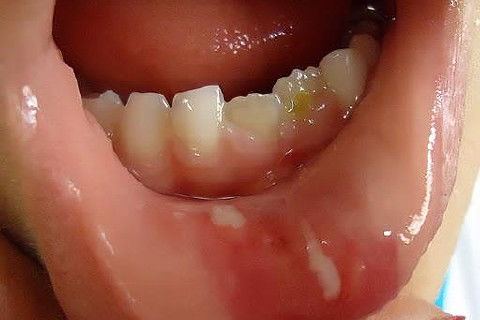

Menino de 6 aninhos sofreu um traumatismo ontem na hora do recreio, lá na escolinha aonde atendo, bateu a boquinha na mesa na hora do lanche.

Examinei-o e constatei ter sofrido apenas uma concussão.

CONCUSSÃO é o trauma dentário menos agressivo que se apresenta.

Sem consequências aparentes ao exame clínico, nenhum dano ao tecido dentário, com pequena agressão aos tecidos de suporte e os dentes apresentam pequena sensibilidade ao toque.

Obs: As duas últimas fotos foram tiradas hoje (24 hs depois).

Fotos do caso